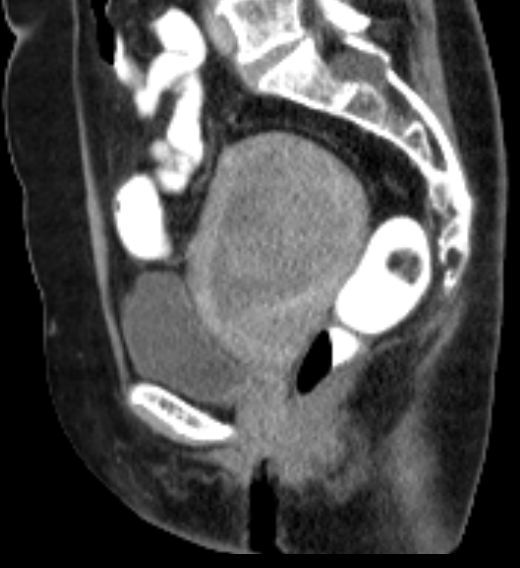

69-jährige Frau, die vor 4 Jahren ein Mammakarzinom hatte und adjuvant mit Anastrozol behandelt wird.

Wegen PM-Blutung wurde eine Abrasio durchgeführt, die einen malignen Müllerschen Mischtumor des Endometriums ergab.![]() |